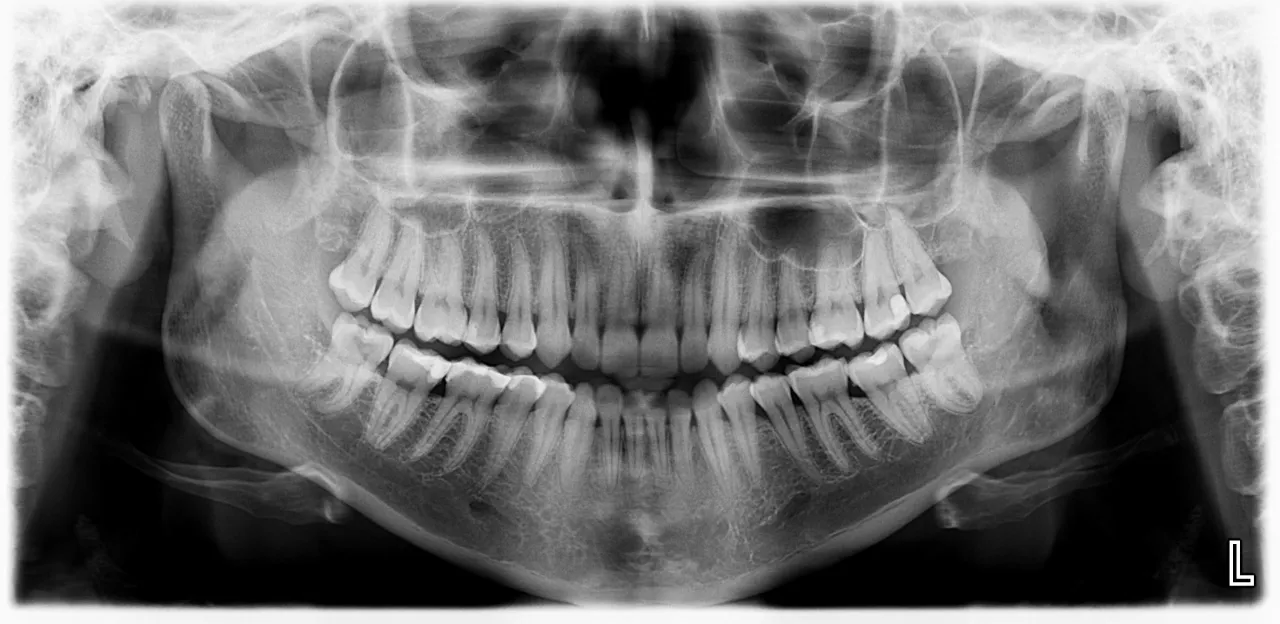

Zrozum swój pantomogram: Gdzie szukać oznaczeń zębów na zdjęciu RTG?

Pantomogram, czyli panoramiczne zdjęcie rentgenowskie, to jedno z najczęstszych badań diagnostycznych w stomatologii. Na takim zdjęciu często widoczne są oznaczenia zębów, zwłaszcza jeśli są one problematyczne lub wymagają szczególnej uwagi. Zazwyczaj numeracja w systemie FDI jest naniesiona bezpośrednio na obraz lub w jego pobliżu, co ułatwia identyfikację. Szukaj dwucyfrowych numerów umieszczonych obok poszczególnych zębów. Czasami na zdjęciu mogą być również strzałki lub okręgi wskazujące na konkretne zmiany, takie jak ubytki, stany zapalne czy zęby zatrzymane (np. ósemki). Zrozumienie numeracji pozwoli Ci lepiej interpretować to, co widzisz na zdjęciu, i świadomie rozmawiać z dentystą o wynikach diagnostyki. To kolejny krok do pełnego zrozumienia stanu swojego uzębienia.